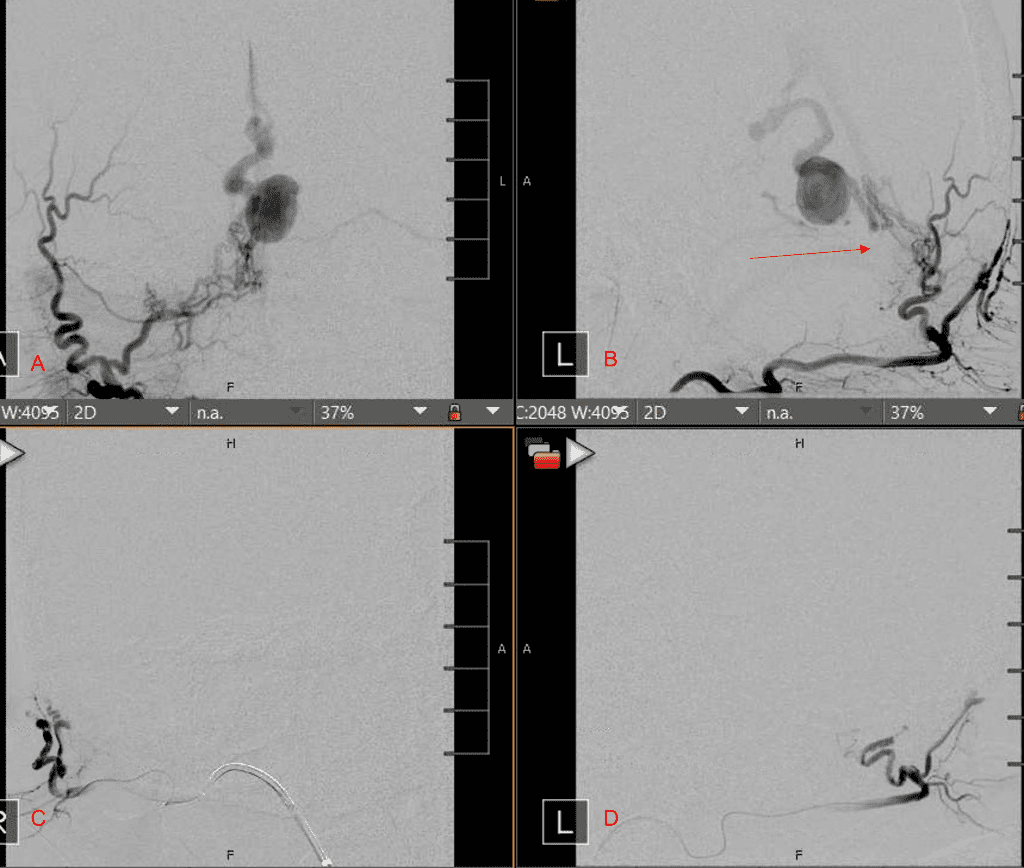

No severe neurologic deficits were observed initially. Her cerebral angiogram revealed a high flow Dural arterial venous fistulous malformation of the tentorium supplied by the bilateral external carotid and left vertebral arteries into a large venous varix within the fourth ventricle at the site of the hemorrhage. Deep venous drainage is observed into the Galenic and Straight Sinus of the posterior fossa (Figure 2).

Figure 2. [A] Ruptured Varix/Aneurysm of the Deep Venous Posterior Fossa drainage and AV shunting (arrows) [B] Posterior Meningeal Artery Fistula [C] Right Middle Meningeal Artery Fistula [D] Post embolization Left Vertebral Angiogram demonstrates resolution of the high flow and pressure A-V Shunting following successful embolization with liquid embolic (NBCA).